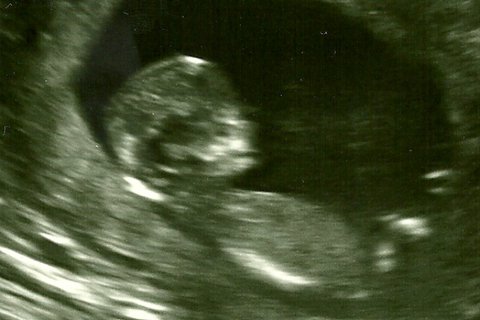

The state of Texas, which was subject to a landmark Supreme Court ruling today, is one of a handful of states requiring not only that abortion providers perform an ultrasound, but that they both…